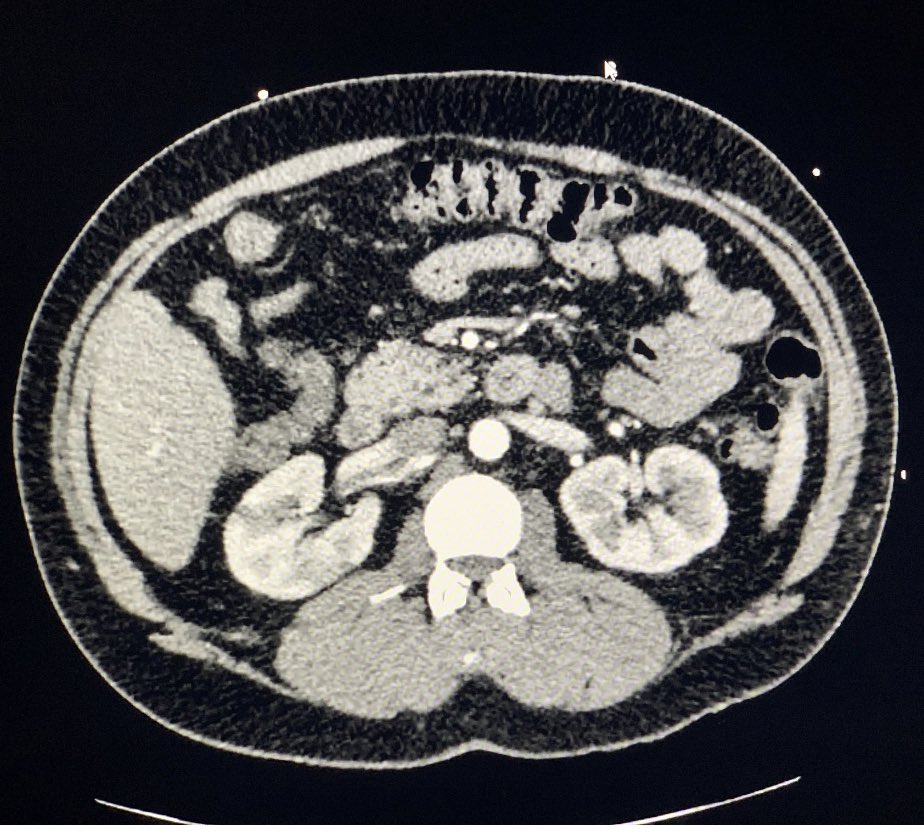

Sudden onset flank pain. When it feels like his previous kidney stone, but it’s not. “January 2021 US Case” by @IUEM_ultrasound on #Vimeo vimeo.com/503226104?ref=…